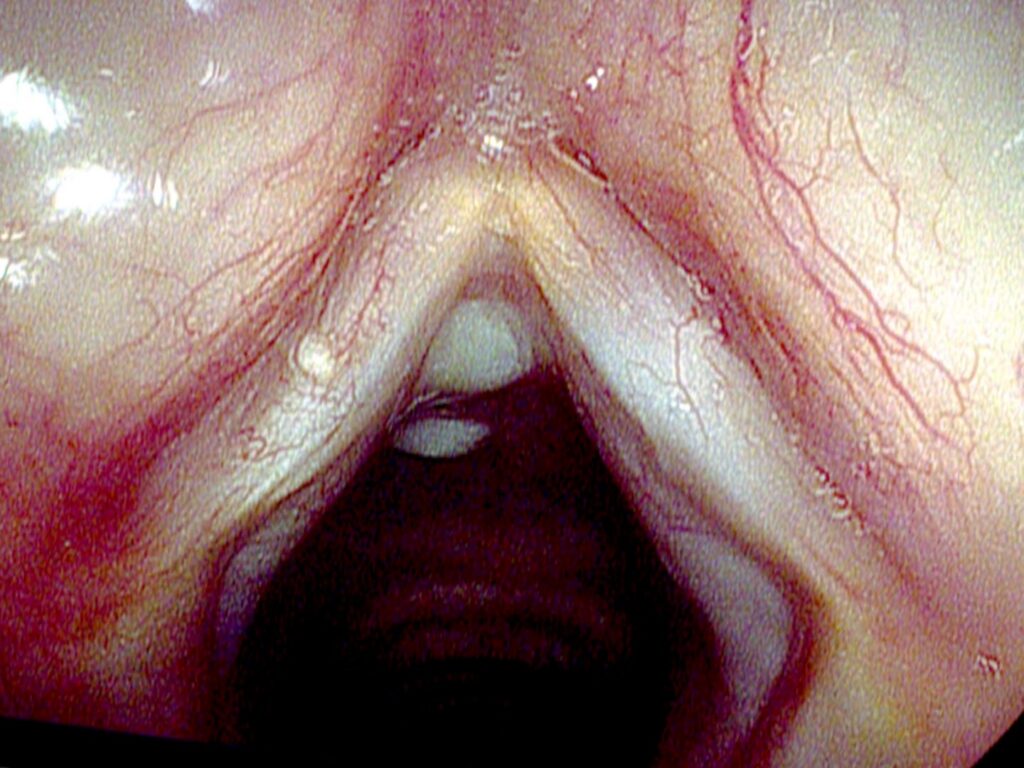

Sarah had a vocal nodule stripped from one cord years ago. Her speaking voice sounds fine, but through most of her middle and upper range, her voice deteriorates and breaks up. Using stroboscopy, one cord is very stiff and the other supple. At her lowest notes, the stiffness difference causes different amplitudes but the same pitch — no diplophonia. In her mid-range, the cords go out of sync, each producing a different note, and the diplophonia is very audible. At her highest notes, the stiff cord is pulled so tight it does not vibrate at all, and all the sound comes from the flexible cord — producing a surprisingly clear, single-cord tone.

Linus is 74 and had a vocal cord biopsy revealing cancer, followed by radiation therapy 12 years ago. His voice is rough. On stroboscopy there is a supple mucosal wave on the right; the left cord oscillates, but stiffly. He ends up with two sound sources from asymmetric stiffness. Interestingly, if the left cord were completely stiff and did not oscillate at all, his voice would be clearer — one cord creating a pure pitch, with no competing vibration from the stiff side.